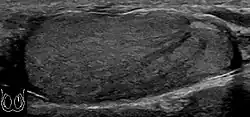

Fibrotic striations

A striated pattern of the testicle, radiating from its mediastinum, does not have clinical importance unless there are alarming symptoms or abnormal signal on Doppler ultrasonography.[8] It is presumed to represent fibrosis.[8]